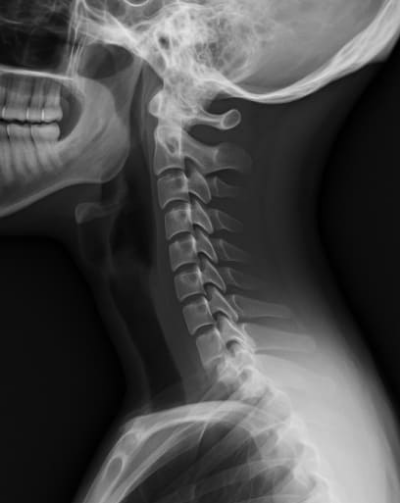

거북목이란 고개가 어깨보다 앞으로 튀어나온 상태를 말합니다. 원래 사람의 머리는 척추 위에 바로 올라가 있어야 이상적인 자세입니다. 하지만 스마트폰, 컴퓨터, 책상 작업이 많아지면서 목이 앞으로 기울어진 형태가 반복되면, 결국 거북목 증상으로 이어집니다.

이러한 상태를 그대로 방치하면 경추의 자연스러운 곡선이 사라지고, 디스크 압력이 증가하며 목디스크의 위험이 커집니다. 따라서 하루 10분만 투자해 거북목 교정운동을 실천하는 것이 중요합니다.